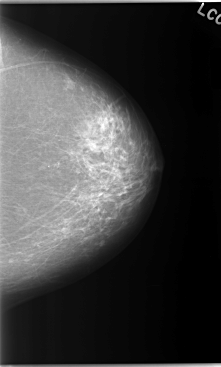

C_0045_1.LEFT_CC

LEFT_CC LINES 5872 PIXELS_PER_LINE 3536 BITS_PER_PIXEL 12 RESOLUTION 50 NON_OVERLAY